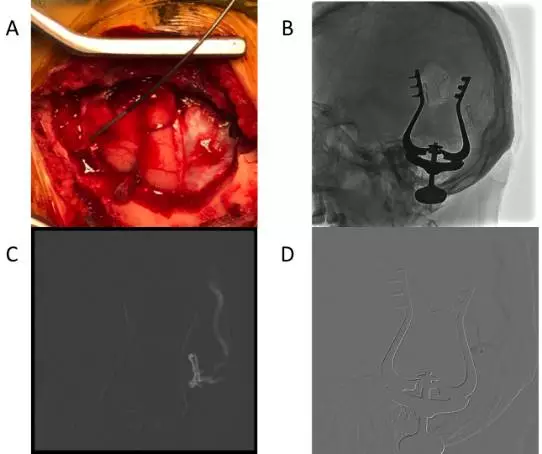

手术经过:在复合手术室(Hybrid operation room),患者经气管插管全身麻醉后。首先经右侧股动脉穿刺置鞘,选用造影导管超选至左侧颈外动脉进行造影,并利用不透射线的刻度尺进行定位(图5A)。在正侧位造影后,利用刻度尺的定位左侧脑膜中动脉靠近瘘口且较为平直的一段,画出该段血管的体表定位(图5B、5C)。根据该段血管的体表投影线做一直切口(图5D),暴露该段脑膜中动脉,结扎近心端后,剪开硬脑膜,离断该段脑膜中动脉,在不塑形的0.014in的Synchro微导丝带领下,直接通过血管断端远端插入Echelon-10微导管(图6A)。通过手推造影确认微导管插入血管为靶血管后(图6B),在路图条件下(图6C),在Synchro微导丝带领下将Echelon-10微导管超选至瘘口,并通过手推造影确认微导管位置(图6D)。随后,缝扎血管断端远端,利用缝线扎紧微导管,阻断注胶时的反流,即“高压锅技术”。造影导管依次超选至双侧颈外动脉,在造影的监测下,阴性路图下通过Echelon-10微导管注入Onyx-18胶1.5ml。复查造影,见瘘口完全被栓塞,引流静脉消失。遂撤除微导管,结束手术(图7)。

图7. A 术中对侧颈外动脉造影显示动静脉瘘瘘口。B 经微导管注入Onyx胶后,术中造影提示对侧颈外动脉不再向瘘口供血。C 同时行同侧颈动脉造影见瘘口仍未完全栓塞,引流静脉仍有显影,但流速较术前明显减慢。D再次注入Onyx胶后,经同侧颈动脉复查造影见瘘口完全被栓塞,引流静脉不在显影。